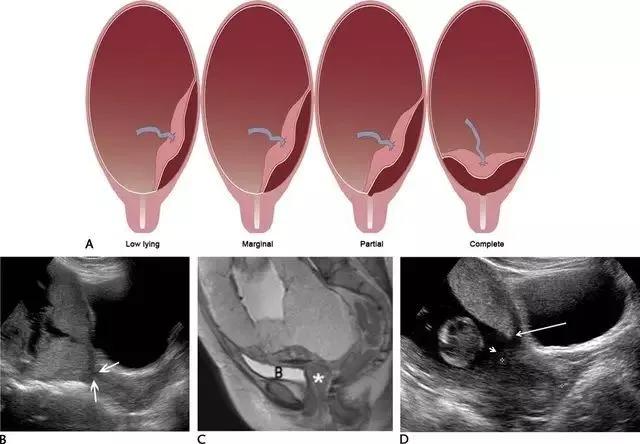

前置胎盘指胎盘覆盖于宫颈内口或位于宫颈内口 2 cm 之内,是晚孕时无痛性阴道出血的重要原因。既往,曾根据胎盘距离宫内口的远近分级为完全性、部分性、边缘性和低置胎盘(图 10)。

2012 年美国妇产科协会对前置胎盘的分类进行了修订,认为边缘性与部分性前置胎盘难以区分,建议只在描述胎盘边缘相对于宫内口的位置。

图 10 示前置胎盘:A 为各种前置胎盘示意图,分别为低置、边缘性、部分性和完全性。B 为孕 20 周的完全性前置胎盘纵切面,箭头示胎盘完全覆盖于宫内口。C 为另一例孕 33 周胎儿的矢状位 T2WI ,星号指胎盘完全覆盖于宫内口。D 为孕 12 周时的低置胎盘矢状面,长箭头示胎盘下缘,短箭头示宫内口,二者距离< 2 cm

推荐经阴超测量胎盘下缘至宫内口距离,若无阴超探头,可选择经会阴超声检查。通常,经腹部超声检查可因胎头覆盖于子宫下段、母体肥胖、膀胱过度充盈或充盈欠佳导致测量不精确。